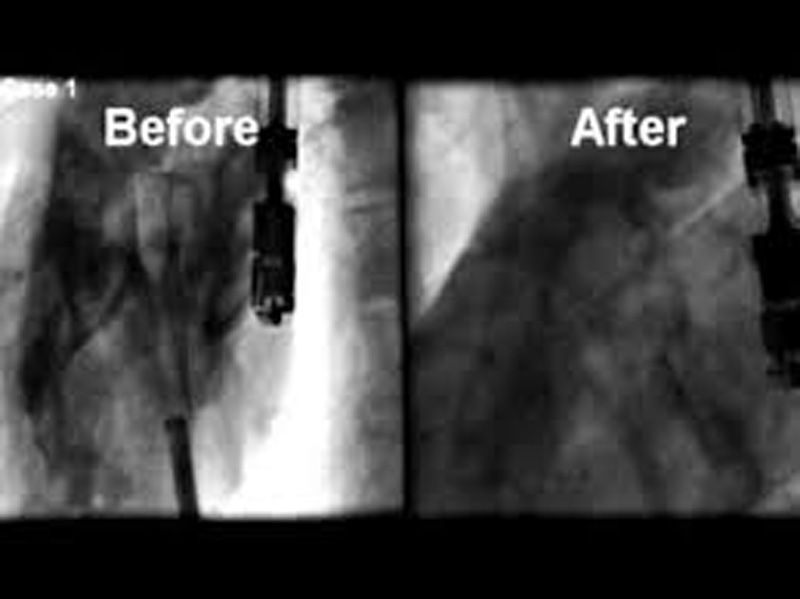

Nobles (cardiochirurgo): "Uno Dei Primi Casi Di Tecnologia

bari cardiochirurgo policlinico rivoluzionaria nobles inchieste puglia eccellenze.